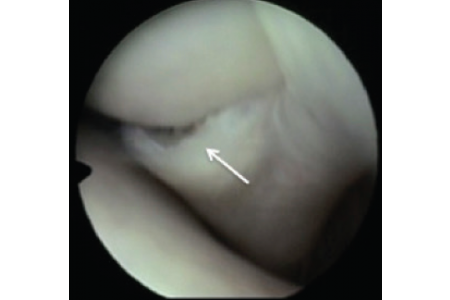

Anaesthetic arthrography of the shoulder is a simple, safe, and reliable diagnostic test to confirm shoulder joint pain and simultaneously identify a lesion. This procedure may be of particular...